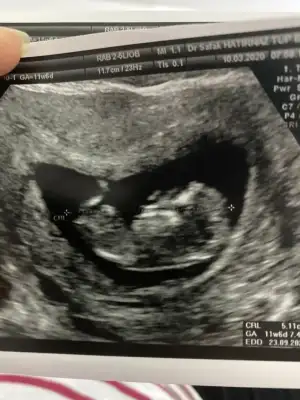

merhaba 12 haftalık hamileyim bende bugün ikili tarama yaptırdım cinsiyet tahmininizi alabilir miyim :)

Eklentiler

• E5C92BC7-7E7F-4A45-8611-64A3B20844EA.webp

E5C92BC7-7E7F-4A45-8611-64A3B20844EA.webp

40,6 KB · Görüntüleme: 51

• A6DDA7B7-A56E-42F6-8D66-E4AAC8182DA4.webp

A6DDA7B7-A56E-42F6-8D66-E4AAC8182DA4.webp

26,7 KB · Görüntüleme: 46